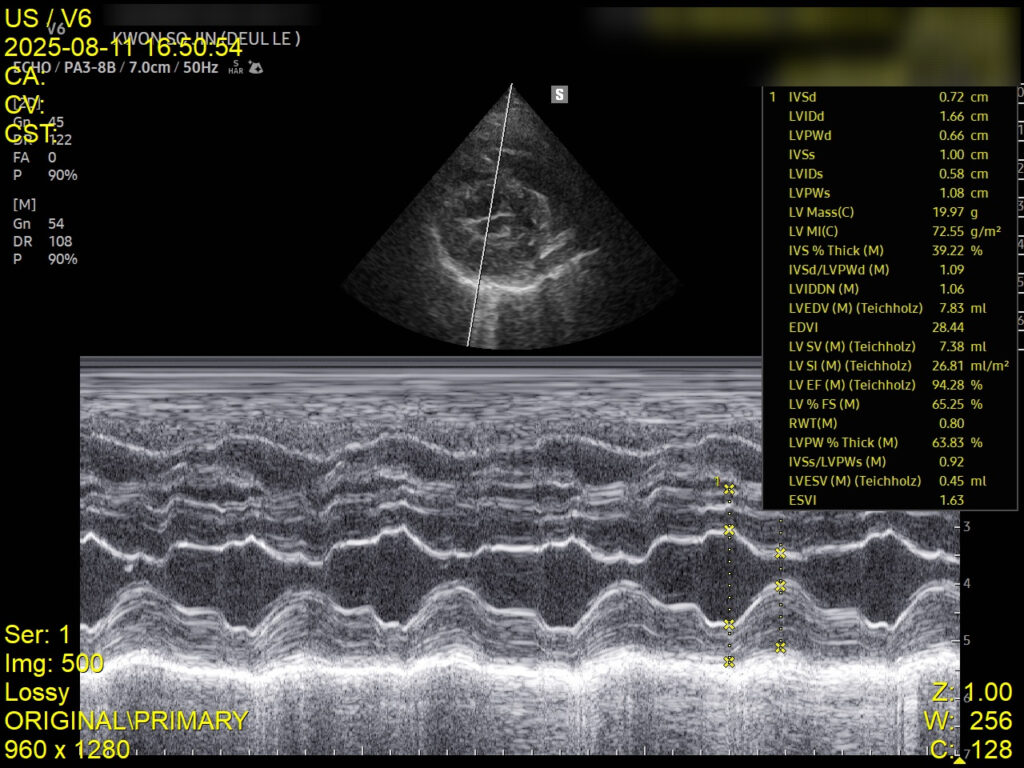

4. 심장초음파 검사

심장초음파에서는 좌심부전 소견은 없었으나, 폐성고혈압이 확인되어 이에 대한 약물 치료가 병행되었습니다. 이는 호흡곤란의 주 원인이 심장이 아닌 폐 자체의 염증성 병변임을 뒷받침하는 결과입니다.

심장초음파 검사 사진 / 출처: 강서 YD동물의료센터